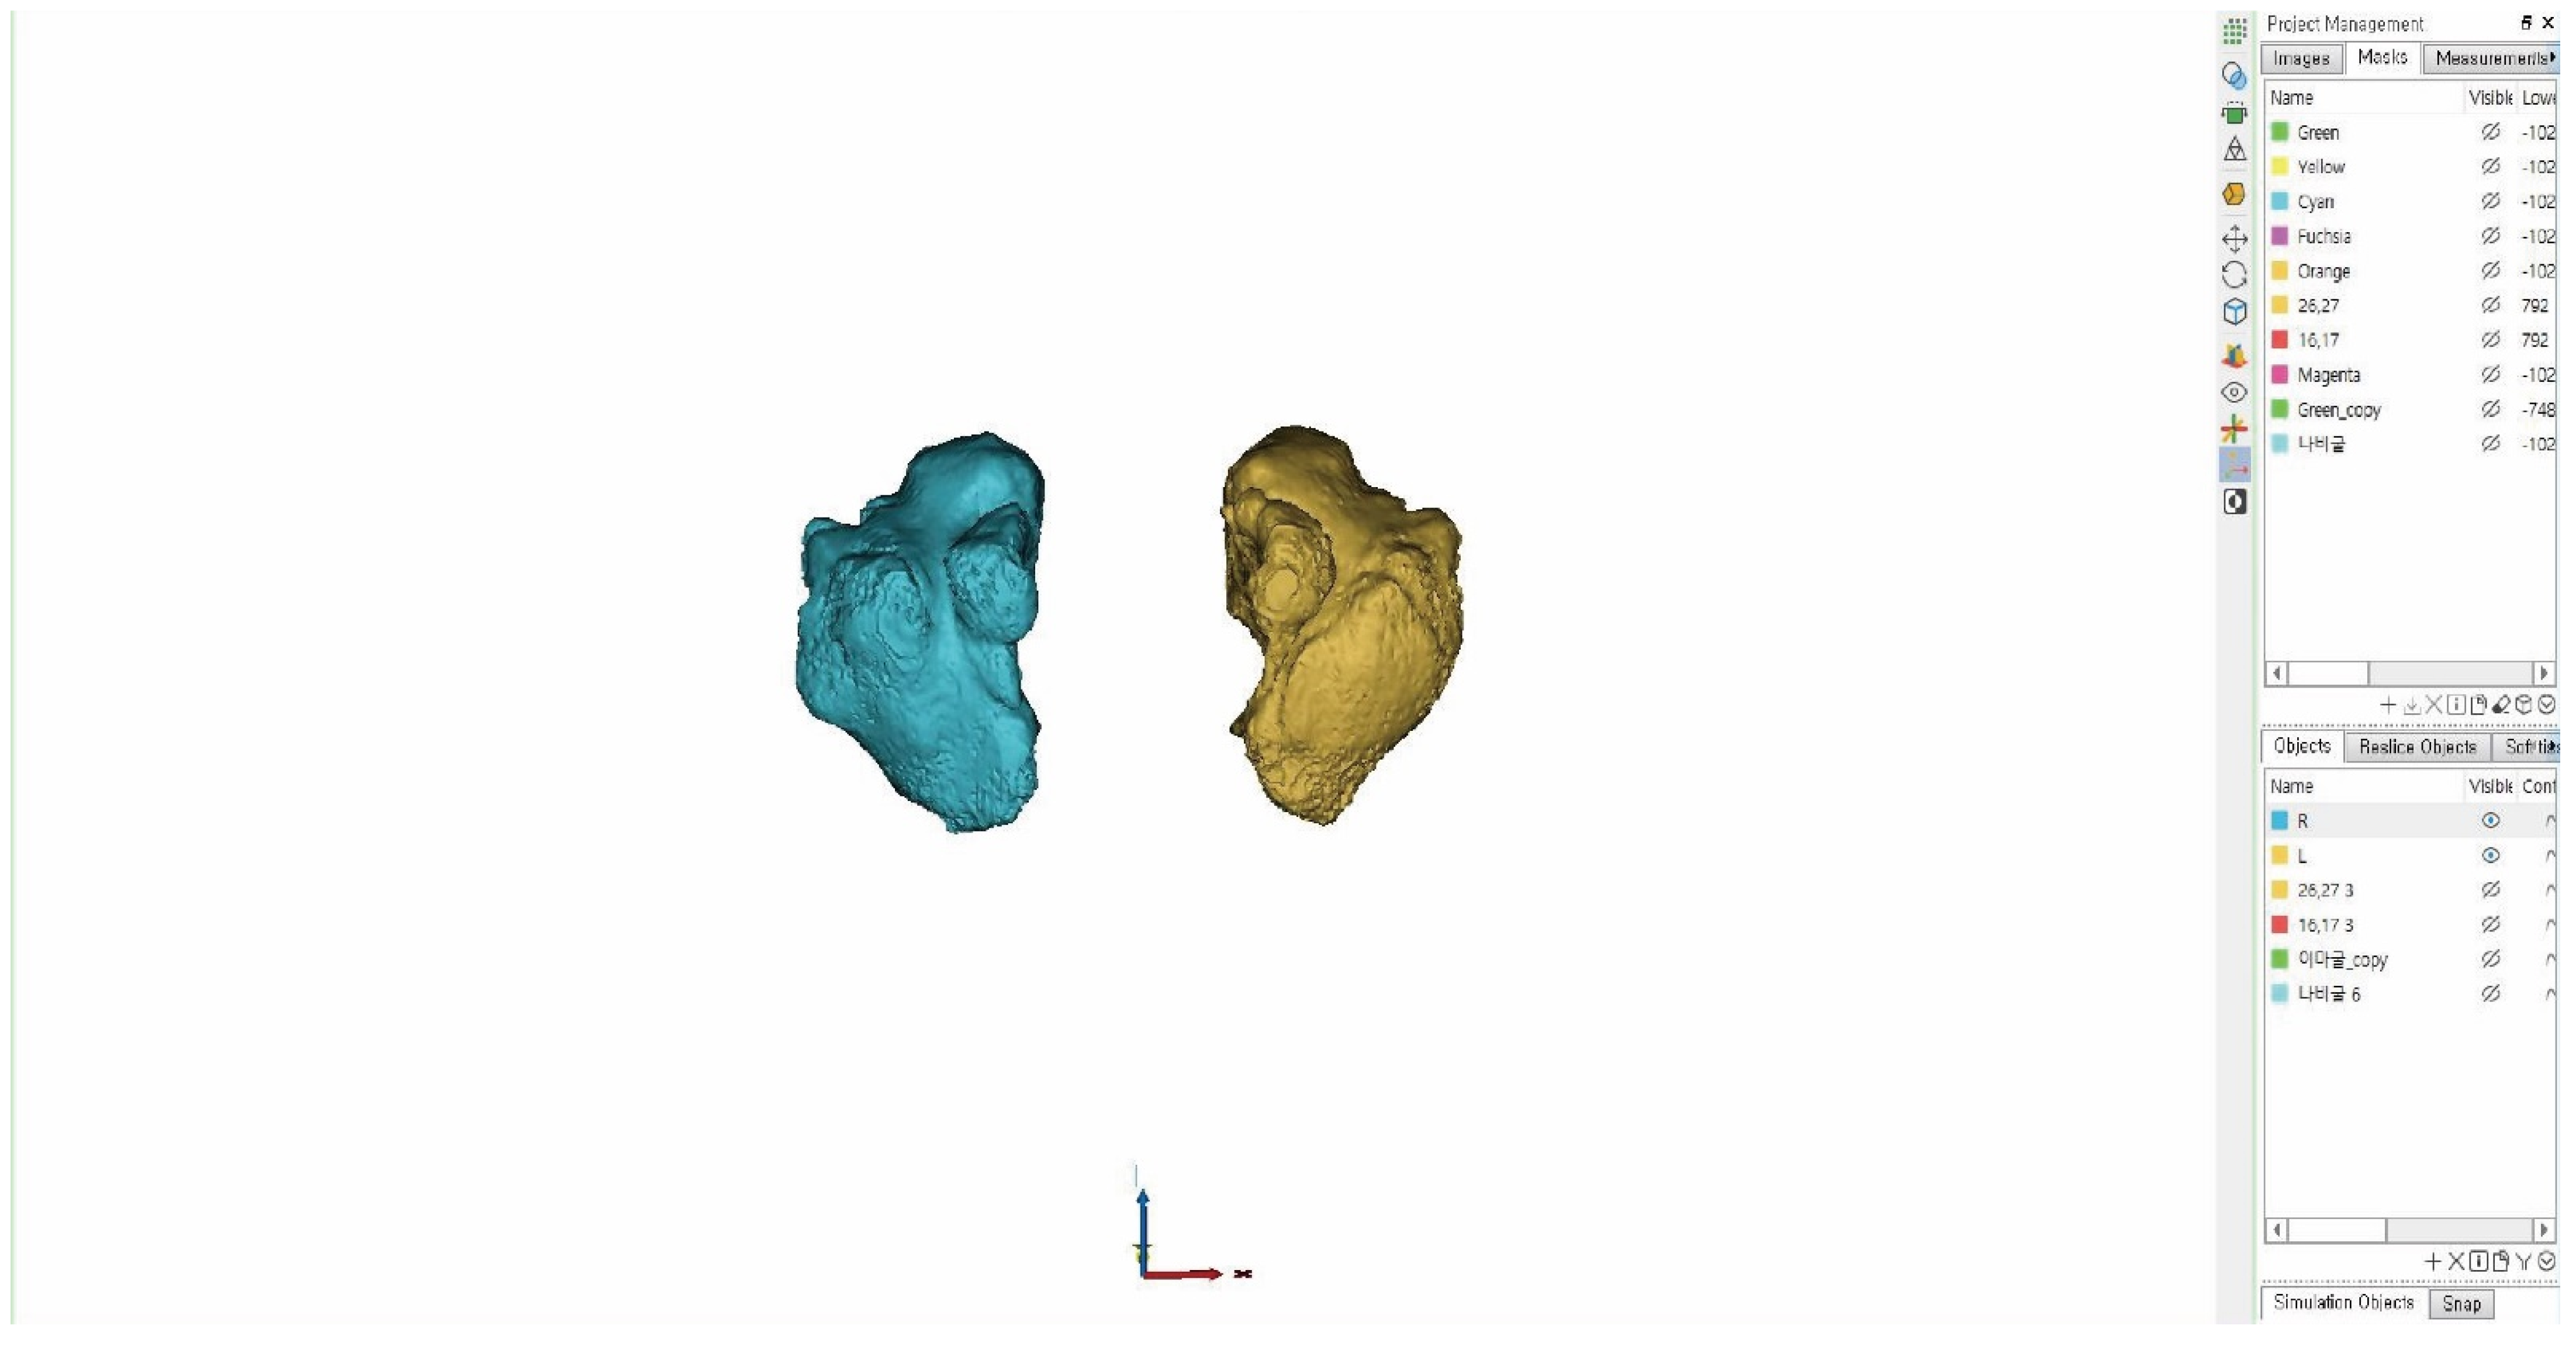

2.2.1. D Image Creation

2.2.2. Measurement Items